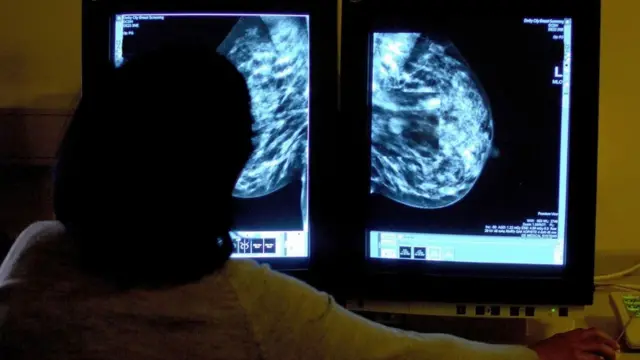

حتی وقتی که پزشکان آگاه باشند، به دلیل مشکلات سیستم همچنان دسترسی افراد تراجنسی به آزمایشهایی که میتواند نجاتبخش باشد دشوار است.

الیسون برنر، سرطانشناس و متخصص هویت جنسی، میگوید: "در بریتانیا افراد بر اساس جنسیتی که با آن در سیستم پزشکی ثبت شدهاند به غربالگریهای سرطان دعوت میشوند."

معنایش آن است که هزاران مرد تراجنسی تست دهانه رحم و معاینه پستان را از دست میدهند، در حالی که زنان تراجنسی برای غربالگری سرطان پروستات فراخوانده نمیشوند.